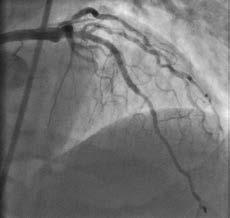

Coronary angiogram immediately following successful stenting of the occlusion using the reverse controlled antegrade and retrograde tracking (CART) technique. Allina Health Minneapolis Heart Institute was the first center in the Upper Midwest to use this novel approach to open chronic total occlusions and it now trains interventional cardiologists at other regional centers in using the technique.